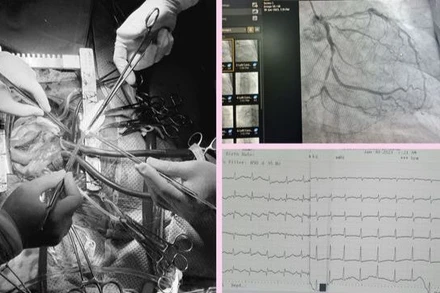

Khoảng 15 phút sau khi bắt đầu trận pickleball, người đàn ông xuất hiện cơn đau ngực nặng, đau lan lên cổ, khó thở, vã mồ hôi nhiều.